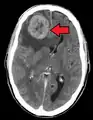

- الدماغ: الأعراض العصبية مثل الصداع، التشنجات، والدوار

تختلف أعراض وعلامات النقائل باختلاف موقع الورم. في البداية، تُصاب الغدد الليمفاوية المجاورة في وقت مبكر. وأكثر المواقع عرضًة للانتشار من الأورام الخبيثة الصلبة[6] هي الرئتين، الكبد، الدماغ والعظام.